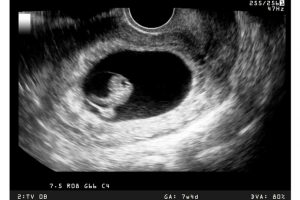

கலக்கத்தில் மருத்துவர்கள் கூறிய அறிவுரைகளை பின்பற்றிய போதிலும் சிறுமியால் வலியிலிருந்து விடுபட இயலவில்லை. இந்நிலையில், மருத்துவர்கள் சிறுமியின் வயிற்றை சோதித்து பார்த்தபோது, வயிறு லேசாக வீங்கியிருந்தது போன்று தெரியவந்துள்ளது. இதனால் மருத்துவர்கள் ஸ்கேன் செய்து பார்த்தபோது திடுக்கிடும் உண்மைகள் வெளியாகின. அந்த சிறுமி 3 மாத கர்ப்பிணியாக இருந்து வந்ததை மருத்துவர்கள் அவருடைய பெற்றோரிடம் கூறியுள்ளனர்.